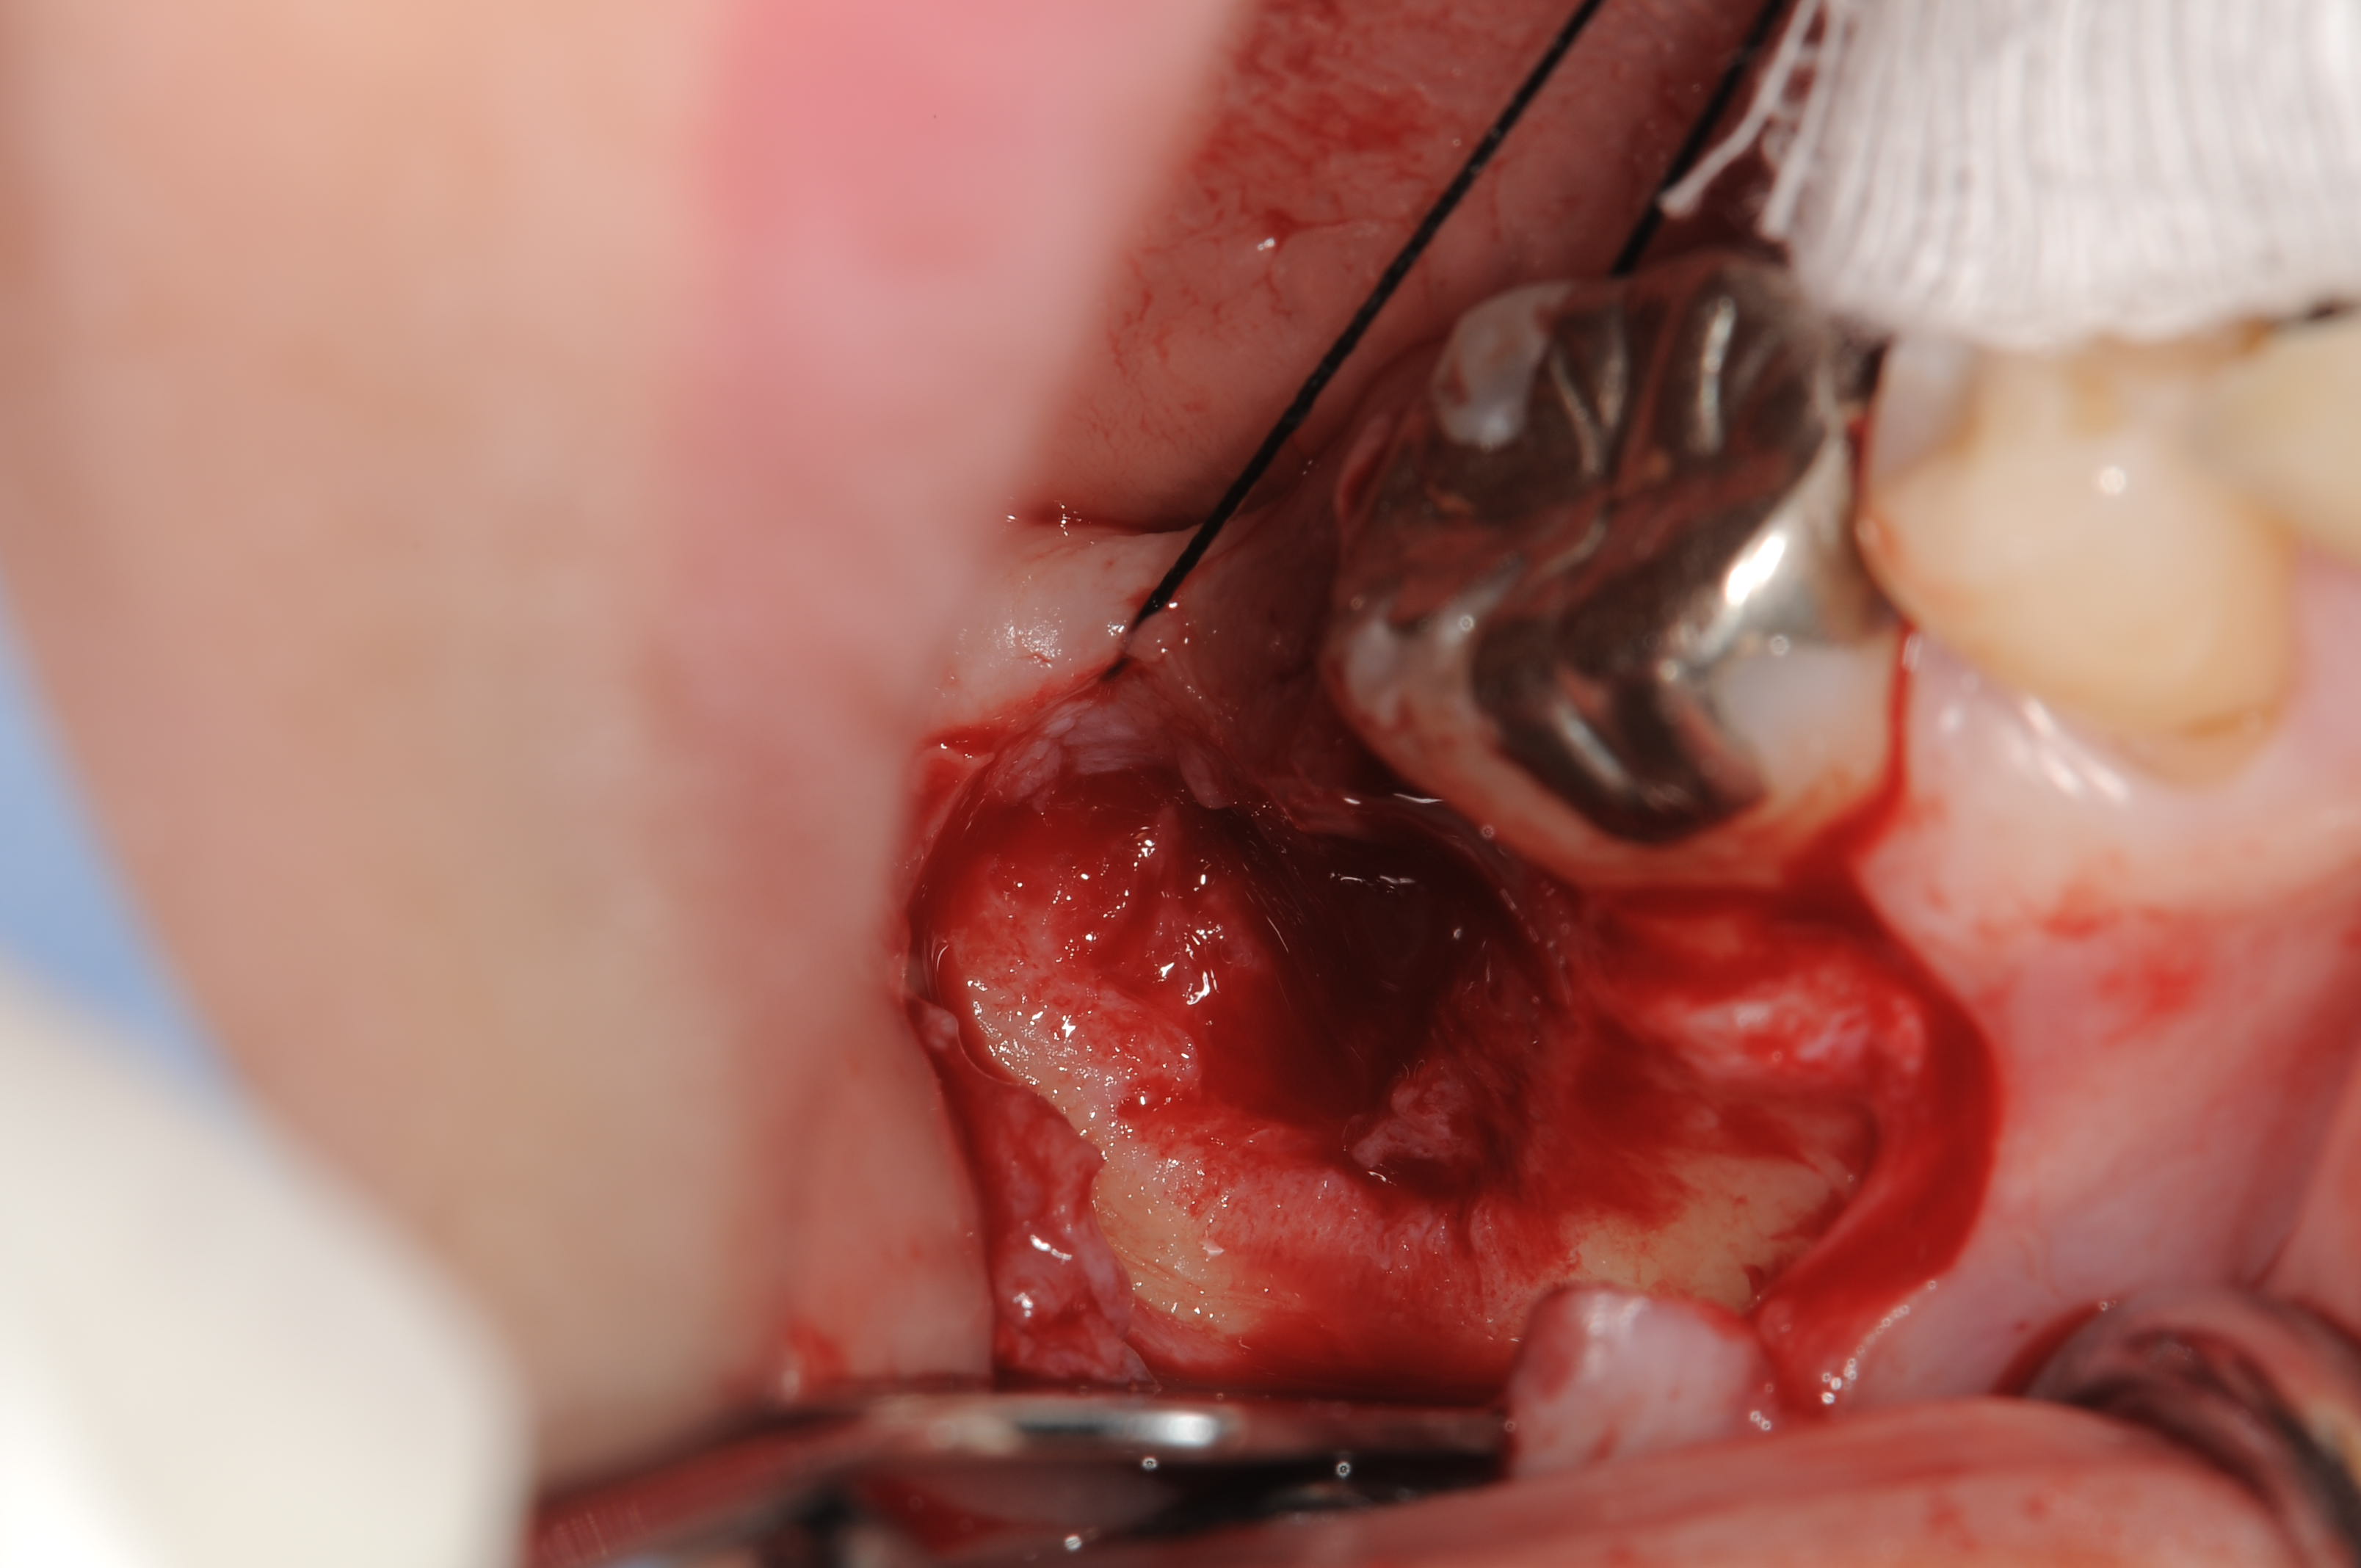

抜歯窩の窩底の骨3mm程度で、かろうじて固定を得て、スプラインHA5.0Φ10mmをnu-ossとバイオメンドエクステンドも用いて、GBR同時埋入しました。

術前のインプラント埋入部位ですが、骨の欠損がはなはだしいです。

大きく陥没し、頬側の骨壁がありません。

スプラインHA埋入と同時にゼノグラフトとコラージェンメンブレンでGBRしています。

埋入後は、形態がボリュームアップしているのがわかります。

特に、減張切開はせずに被覆できました。